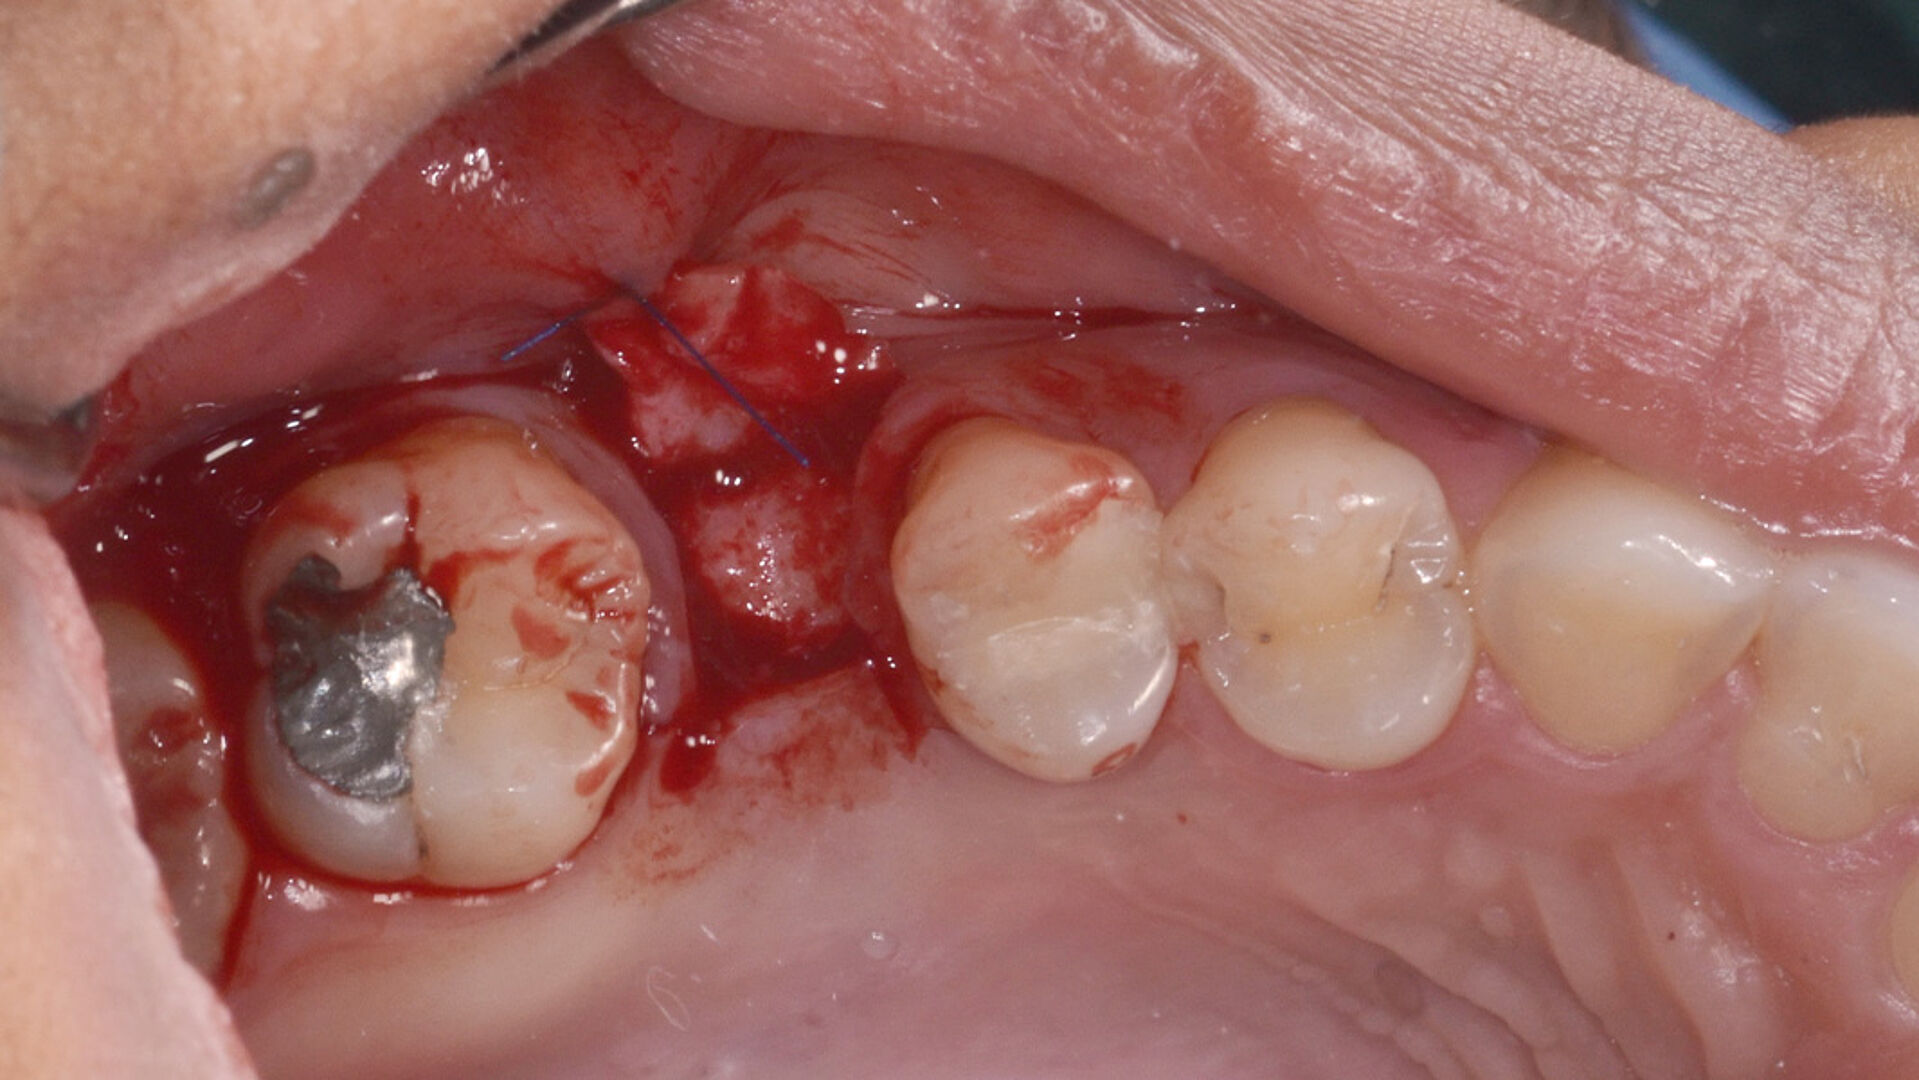

Die transgingivale Einheilung dentaler Implantate ist ein wissenschaftlich gut untersuchtes und klinisch erfolgreiches Verfahren. Für die transgingivale Einheilung sollten die Implantate primärstabil inseriert werden, nur kleine Hartgewebeaugmentationen notwendig sein und ausreichend stabiles Weichgewebe vorliegen. Um in Fällen mit Augmentationsbedarf das iSy Implantatsystem verwenden zu können – ohne die Implantatbasis demontieren zu müssen – bietet das iSy System Implantate mit gestecktem Einbringpfosten an. Nach gedeckter Einheilung und Freilegung des Implantats können drei verschieden breite Gingivaformer eingebracht und im Anschluss sowohl eine digitale als auch konventionelle Abformung durchgeführt werden. Die entsprechenden Abformpfosten und Esthomic Abutments gibt es ebenfalls in drei verschiedenen Emergenzprofilen, welche formkongruent zu den Gingivaformern sind. Im folgenden Fall wurde ein geringes bukkales Knochendefizit mit einem Gemisch aus Eigenknochen und PRF (Plättchenreiches Fibrin) augmentiert und das Weichgewebedefizit mit einer azellulären dermalen Matrix (NovoMatrix/ BioHorizons) aufgebaut.

Nicht nur die korrekte dreidimensionale Positionierung der Implantate, sondern auch das Know-how der Knochenaugmentation und die entsprechende Manipulation des Weichgewebes sind essenziell für den Erfolg. Die Kieferknochenrekonstruktion mit autologen Knochenblöcken, die nach der Beschreibung von Prof. Dr. F. Khoury ausgedünnt werden, sowie das Auffüllen der entstandenen Hohlräume mit autologen Knochenspänen führen zu einem vorhersagbaren, langzeitstabilen laminären Knochen. Auch das Implantatdesign mit der parallelwandigen Schulter sowie das Platform-Switching tragen maßgeblich zur erfolgreichen Rekonstruktion bei. Ein weiterer Vorteil des iSy Implantatkonzepts ist die Implantatbasis. Bei transgingivaler Einheilung verbleibt sie bis zur endgültigen Versorgung auf dem Implantat. Die Manipulation des Weichgewebes durch häufigen Abutmentwechsel hat laut Studien einen beachtlichen Anteil an Knochen- und Weichgewebsveränderungen. Auch bei gedeckter Einheilung werden ab dem Zeitpunkt der Freilegung mithilfe der Implantatbasis Abutmentwechsel minimiert.

Für den langfristigen Erhalt einer Implantatversorgung müssen unterschiedliche Entscheidungsfaktoren gegeneinander abgewogen werden. So spielen die anatomischen Voraussetzungen eine ebenso große Rolle wie die Wahl der prothetischen Versorgung. Doch auch die Wünsche der Patienten in Bezug auf Ästhetik und Funktion ihres späteren Zahnersatzes in Abhängigkeit ihres zur Verfügung stehenden Budgets gilt es zu berücksichtigen. Nach Abwägung all dieser Kriterien muss die Entscheidung für den richtigen Implantationszeitpunkt gewählt werden. Trotz des Trends zu Sofortversorgungsprotokollen ist die Spätimplantation im Seitenzahnbereich das risikoärmste Implantationsverfahren in Bezug auf den Zeitpunkt des Eingriffs, denn der Kieferknochen bekommt Zeit, um nach dem Zahnverlust auszuheilen und die Alveole mit Knochengewebe zu durchsetzen. Falls eine Socket Preservation oder aufgrund eines defizitären Kieferknochens eine umfassende Augmentation nach der Extraktion erforderlich sind, kann sich die durchschnittliche initiale Heilungsphase von zirka drei Monaten auf sechs oder mehr Monate verlängern. Nach erfolgter Regeneration des Kieferknochens und des Weichgewebes sind die besten Voraussetzungen für eine komplikationslose Implantation geschaffen.